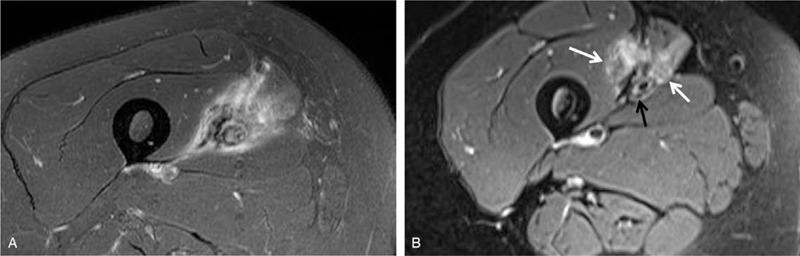

We diagnosed it as obstruction of the superficial femoral artery and vein caused by external compression of the MO between the sartorius and vastus medialis of the thigh.

我们诊断为大腿缝匠肌和股内侧肌之间的MO外部压迫导致股浅动脉和静脉阻塞。